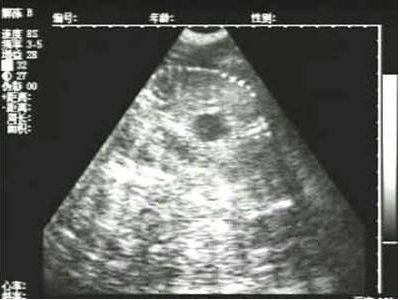

需要注意的是,出現云團狀必須雙側檢查加以確認.根據B超機顯示圖我們大致可以判斷孕齡.圖像呈橢圓或者卵圓形大致為30天左右孕齡;圖像呈橢圓形或者卵圓形外,有明顯發亮骨骼圖像大致為50孕齡左右;圖像囊胚消失,發亮處隱約可見竹節狀東西為成型胎兒骨骼,一般為后期80孕齡以后。一般B超機成像會出現三種顏色,白色、黑色、灰色。白色為密度較高的物體,如骨骼或者結實.黑色一般為液體,包括血液、羊水、組織間隙液體、炎癥病灶等?;疑话銥閷嵸|性物質,如肌肉。

獸用B超機檢測母豬胎兒骨骼圖像

懷孕后期胎兒骨骼圖像